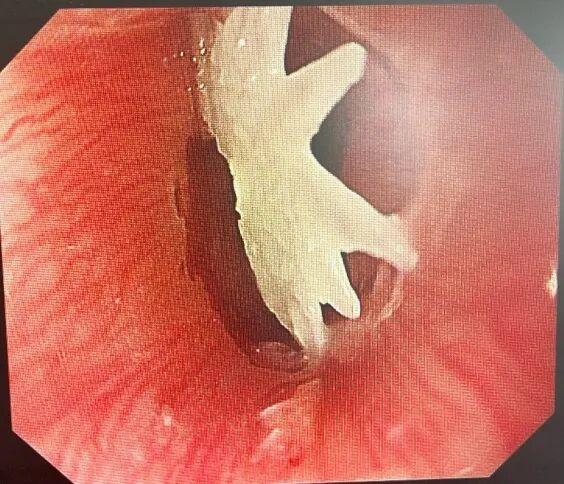

在内镜中心的配合下,消化科团队紧急开展胃镜检查,检查发现一枚不规则鱼骨竟带着多个锋利尖刺,部分已刺入宝宝娇嫩的食管壁,稍有不慎就可能划伤血管、引发穿孔。

凭借丰富经验,完整取出“肉中刺”

最终,凭借丰富的内镜经验,手术团队小心翼翼操作,终于将这颗 “肉中刺”完整取出,家长看着带血的鱼骨,后怕不已。